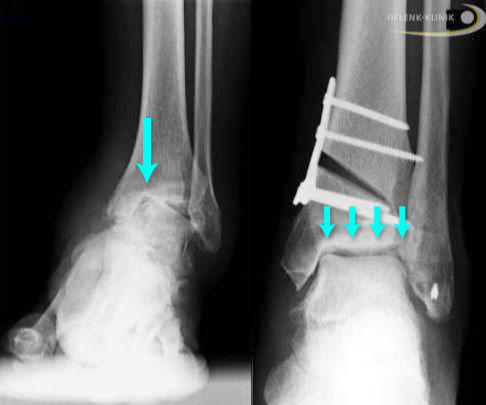

Osteotomie am Außenknöchel: Fehlverheilte Wadenbeinfraktur

Bei fehlverheilten Knöchelfrakturen kann das Wadenbein verkürzt zusammen gewachsen sein und sich nach außen verdreht haben. Daraus ergeben sich Fehlstellungen des betroffenen Fußes, z. B. ein Knickfuß. Ist die Syndesmose ebenfalls verletzt, passt die Weite der Sprunggelenkgabel nicht mehr korrekt.

Die operative gelenkerhaltende Therapie soll die physiologische Gelenkstellung und die normale Sprunggelenkachse stufenfrei wiederherstellen (Reposition). Der Spezialist wendet dazu unterschiedliche Osteotomietechniken an, bei denen die Position der betroffenen Knochen umgestellt wird. Er durchtrennt gezielt den Wadenbeinknochen und entfernt gegebenenfalls einen Knochenkeil. Nachdem die Knochenanteile in ihre korrekte Lage gebracht wurden und die neue Länge und Stellung des Wadenbeins überprüft wurde, fixiert der Spezialist die Bruchstücke zueinander mit Schrauben und Platten (Osteosynthese).

Durch die Trennung und Einheilung der betroffenen Knochen in neuer Position kann der Fuß- und Sprunggelenkspezialist häufig die anatomische Form und somit die Belastungsfähigkeit des Sprunggelenks wieder herstellen.

Eventuell versorgt der Operateur gleichzeitig Syndesmosenverletzungen. In manchen Fällen stabilisiert er die Sprunggelenkgabel durch eine kaum einschränkende Versteifung der unteren Verbindung zwischen Schienbein und Wadenbein.